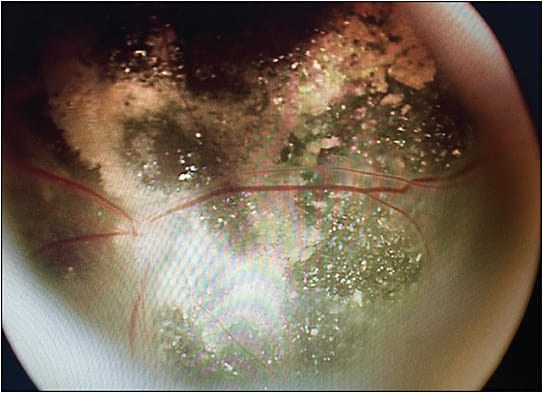

Early in my career, when I first began treating children with ROP, I performed surgeries in stage 5 cases but stopped for a period of time, believing that the procedures weren’t accomplishing much. However, months and even years later I had opportunities to reexamine many of the children on whom I had operated and many I hadn’t. Comparing the two groups, I saw the benefits of light perception vision that the surgeries had accomplished. The children’s parents and families often told me how significant it was in their lives. Light perception allows the children to know whether it’s day or night and whether to sleep or wake. It also allows them to better orient themselves as they perceive their surroundings, for example, a nearby door or window. For children who have never been able to see details, this type of vision helps them to ambulate and orient themselves to time and space. Once that became clear to me, I reversed my previous decision and began performing the surgeries again (Figure 1).

Because the retina is completely detached in stage 5 ROP, the goal of surgical intervention is to achieve at least partial reattachment. This may enable light perception, and it may also prolong the survival of the eye itself by preventing phthisis. Because of the neovascularization and fibrovascular proliferation that has occurred in stage 5 ROP eyes, the funnel retinal detachments are typically tractional rather than rhegmatogenous. The more vitreous that can be released during surgery, the more likely at least some of the retina will reattach.

The challenge at this point is determining where to begin removing the sheath of vitreous that has formed in a circumferential and radial pattern and closed the funnel anteriorly. Failure to find the correct plane for opening the funnel and unintentionally engaging retinal tissue renders the surgery a failure. Often, it’s necessary to dissect several layers of membrane to open the funnel. Once inside the funnel, the goal is to remove as much vitreous and membranes as possible without creating a rhegmatogenous component. Once a rhegmatogenous component occurs, the surgical success drops significantly. At the end of a successful case, I like to instill viscoelastic for stabilization and rigidity for closing the eye. At the end of surgery, the retina is opposed to the scleral wall; therefore, laser is not possible or recommended. With time, once the traction is removed, the retina reattaches without the need for vitreous substitutes.